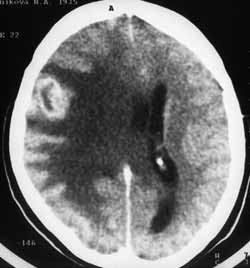

Рис. 3 и 4. (Слева) В правой височно-теменной области отмечается амебовидное снижение плотности белого вещества. После внутривенного усиления накопления контрастного вещества не выявлено. (Справа) Тот же больной. Через 1 месяц четко визуализируется метастаз.